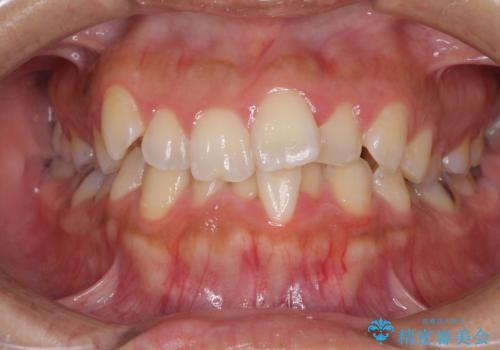

[インビザライン] 前歯のガタつき・すれ違い マウスピース矯正治療